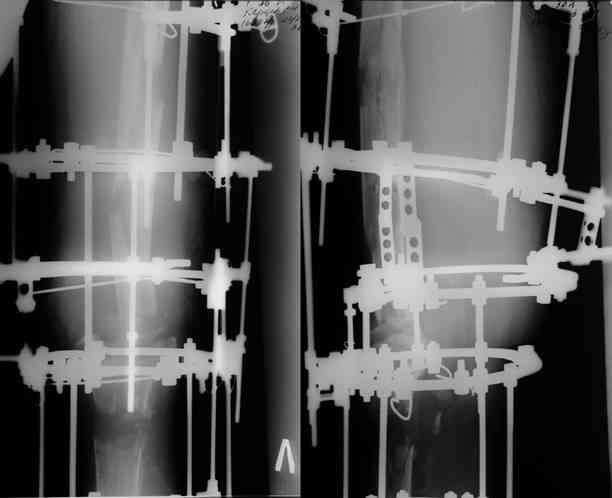

После нескольких некрэктомий, проведения аутодермопластики и заживдения ожоговой раны через 2 месяца после травмы произведен открытый остеосинтез левой бедренной кости штифтом и пластиной (деротационной) [image 01, 02]. Через 1 год и 7 месяцев после травмы у больного диагностированы ложный сустав и хронический остеомиелит левой бедренной кости. Произведено удаление металлических фиксаторов, секвестрэктомия и остеосинтез бедренной костивнешним двухплоскостным стержневым аппаратом [image 03, 04] .

Через 3 года после травмы констатировало отсутствие консолидации бедренной кости, сохранение признаков хронического остеомиелита (свищ в нижней трети левого бедра). Произведен демонтаж аппарата, реостеосинтез бедренной кости спице-стержневым аппаратом, некрсеквестрэктомия. В аппарате удалось лишь частично произвестиустранение углообразной деформации бедренной кости [image 05] .